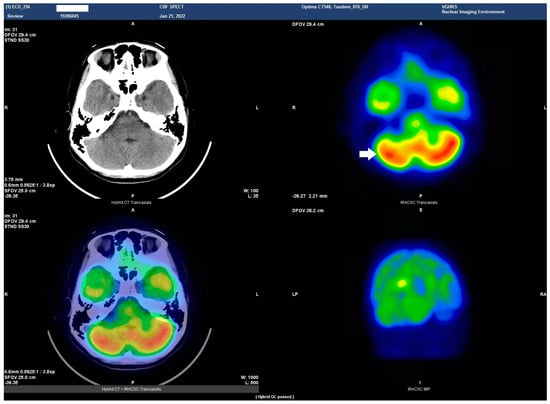

HSAN4 is a rare genetic disorder with a complex clinical presentation. Our hypothesis that the CNS might be implicated in this condition gained substantial support from the clinical manifestations observed in our patient. The presence of spasticity in her feet and a strong positive Babinski’s sign, which are characteristics commonly found in patients with upper motor neuron (UMN) lesions [16], prompted us to explore the potential involvement of the central nervous system (CNS) in HSAN4. To investigate this novel aspect, we employed Tc−99m ECD SPECT imaging for assessing cerebral blood flow and revealing perfusion deficits within the brain [23]. This study represents the pioneering visualization of brain perfusion abnormality in an HSAN4 patient, and the findings are nothing short of groundbreaking. Our Tc−99m ECD SPECT imaging revealed multiple areas within the CNS with perfusion deficits. Notably, these deficits were observed in the cerebellum (Figure 2), thalamus (Figure 3), and postcentral gyrus of the parietal lobe (Figure 4 and Figure 5). These findings suggest that HSAN4 has the potential to affect not only the peripheral nervous system (PNS) but also the CNS, ushering in a new era in our understanding of this complex disorder. One of the most significant and intriguing aspects of our findings is the localization of these deficits in the postcentral gyrus and thalamus. These regions play pivotal roles in processing pain signals transmitted from the spinothalamic and spinoreticular tracts [24]. The spinothalamic and spinoreticular tracts are the central pathway for nociceptive signals, conveying pain information from the peripheral nervous system to the cerebral cortex. The former pathway originates from the dorsal root ganglia, traverses the dorsal horn of the spinal gray matter, proceeds to the ventral posterolateral nucleus of the thalamus, and finally reaches the posterior limb of the internal capsule. The latter tract also handles nociceptive signals, routing them to the thalamus and postcentral gyrus [25,26]. The perfusion deficits we observed in these crucial pain-processing areas offer a profound and novel perspective on explaining the pain insensitivity characteristic of HSAN4 patients. While previous research has primarily focused on the peripheral mechanisms of pain insensitivity, our study provides compelling evidence that the origin of this phenomenon might extend beyond the peripheral nervous system.

In essence, pain insensitivity in HSAN4 involves intricate CNS mechanisms. The perfusion deficits in the thalamus and postcentral gyrus shed light on how HSAN4 may disrupt these critical pathways, leading to the observed pain insensitivity. This revelation challenges conventional thinking and highlights the importance of considering both peripheral and central components in our understanding of HSAN4.

Figure 3. Axial view of the Tc−99m ECD brain perfusion SPECT study. A decreased uptake in the tracer can be observed in the thalamus (arrow). Left upper panel, CT image; right upper panel, SPECT; left lower panel, the combined SPECT and CT images.